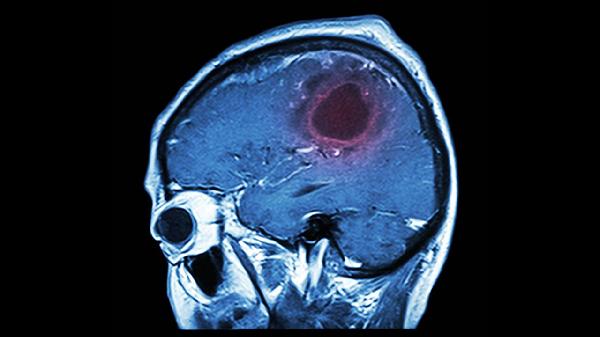

若轻微脑血栓反复发作或伴随意识障碍、剧烈头痛,可能提示大血管狭窄或心源性栓塞等高风险因素。此类情况需进一步完善头颈部血管造影、心脏超声等检查,必要时需行血管内支架置入术或抗凝治疗。未及时处理的轻微脑血栓可能进展为完全性卒中,导致永久性偏瘫或认知功能障碍。